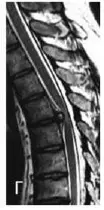

Найлегше було б почати з «модних» гриж дисків. Але наша багаторічна практика (а також світовий досвід) показують, що грижа диска в грудному відділі хребта – це велика рідкість. Нижче наведено МРТ грижі диска грудного відділу хребта – випадок вкрай рідкісний.

Якщо грижа грудного відділу хребта і виявляється на МРТ, то вона, як правило, не є основною причиною болю.